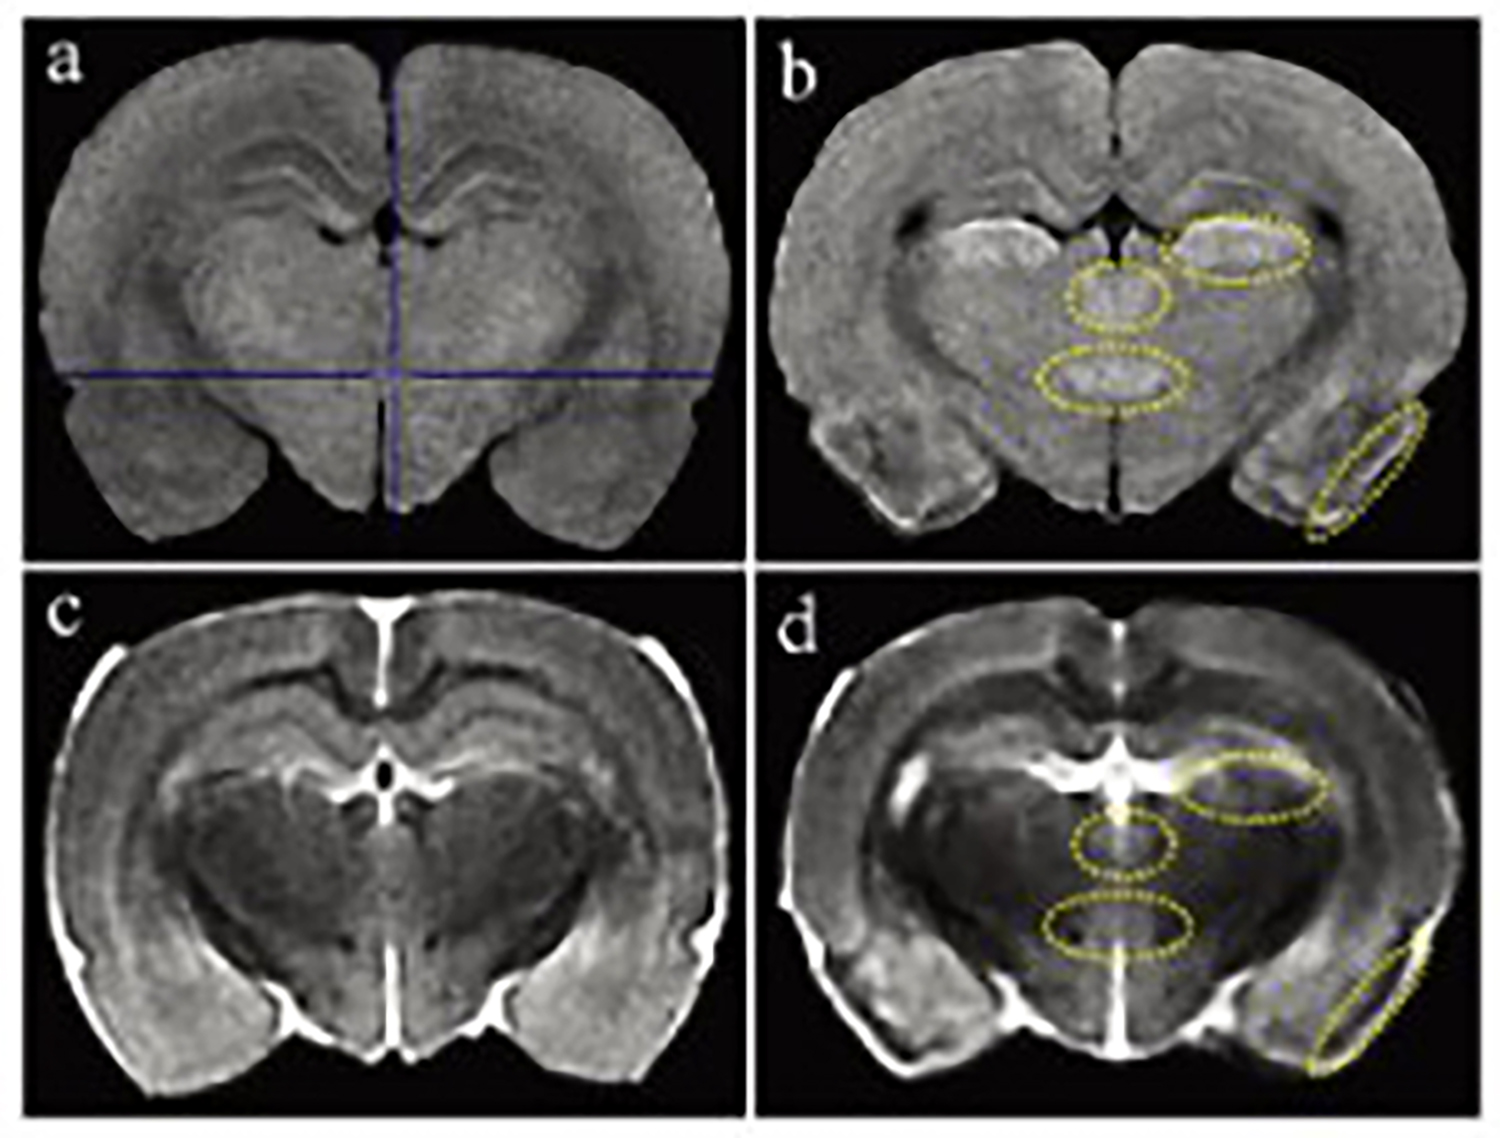

磁共振成像(MRI)广泛应用于临床前研究和药物开发,是一种强有力的无创性方法,可用于评估小鼠疾病模型的表型和治疗效果。

小动物磁共振成像(MRI)是一种强大的非侵入性工具,可用于检测临多种病变。

一个新的紧凑型高性能小动物磁共振成像平台(M3),该系统使用一种新的磁铁设计和一套相关的软件,降低了小动物磁共振成像仪的成本和复杂性。

1.0T小动物核磁共振成像仪是开云足球体育_开云足球(中国)2016年推出的新品,是目前开云足球体育_开云足球(中国)分析磁场强度最高的核磁共振成像仪。